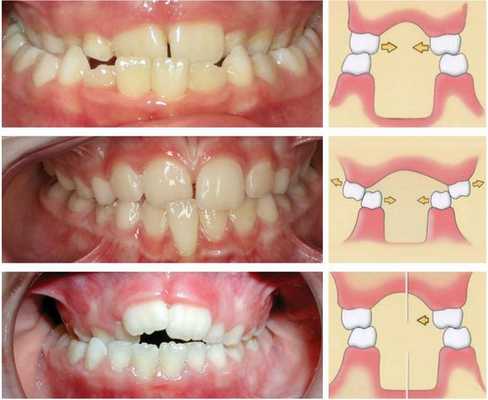

- Скелетный класс 1, т. е. патология находится в области фронтальных зубов. .

- Дизокклюзия слева и справа (вертикальное разобщение верхнего и нижнего зубных рядов) .

- Сужение обеих зубных дуг.

- Вестибулярный наклон клыков верхней челюсти (зубы расположены вне зубного ряда).

- Эндопозиция трёх резцов, т. е. их смещение или наклон кнутри от зубного ряда.

- Тесное положение зубов. . .

Назначено аппаратурное ортодонтическое лечение с применением Эджуайз-техники (брекет-системы) на верхней и нижней челюсти. Ориентировочный срок лечения на основе диагностических данных и диагноза составлял 24-28 месяцев. Сначала брекеты были установлены на верхнюю челюсть.

Спустя 3 месяца клыки стали опускаться. Со стороны височно-нижнечелюстного сустава сохранялся небольшой дискомфорт, но он был не таким сильным, как раньше. Далее были установлены брекеты на нижнюю челюсть.

Спустя 8 месяцев была полностью устранена диастема, пациентка больше не прикусывала щёку, поэтому слизистая была блестящей и бледно-розовой, без изменений.

Через 18 месяцев было исправлено положение зубов и форма зубной дуги, назначено ношение эластиков в жевательном отделе, чтобы добиться плотных контактов между антагонистами (зубами верхней и нижней челюсти, которые соприкасаются при накусывании).

Через 21 месяц контакты между антагонистами восстановились (первый класс Энгля), была устранена скученность, жалобы со стороны височно-нижнечелюстного сустава отсутствовали.

Брекет-систему сняли и зафиксировали несъёмные ретейнеры, также были изготовлены съёмные ретейнеры на обе челюсти. Пациентке рекомендовано носить капы и провести реминерализирующую терапии. Следующий приём назначен через 3 месяца.